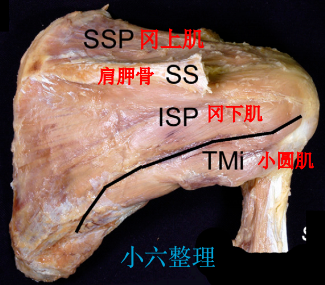

解剖